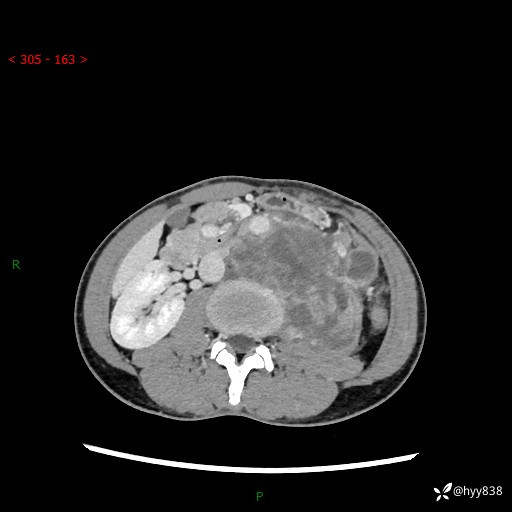

简要病史:患者无明显诱因出现左侧下腹及左侧腰背部疼痛,为间歇性隐痛,我院行胃肠镜检查,提示慢性非萎缩性胃炎,予以口服药物治疗,效果欠佳,后仍觉腹痛不适,遂至当地中医医院就诊,行彩超提示左肾积水及左肾实质性占位,遂来我院泌尿外科就诊

腹部CT平扫+增强